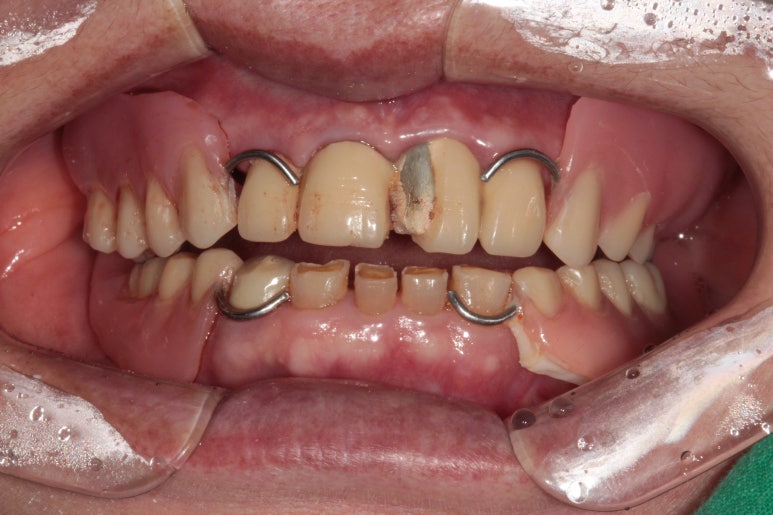

처음 오셨을 때 촬영한 정면 구강 내 사진입니다.

위 앞니 보철물은 도재 (포세린,porcelain)가 깨져있어 보기 흉한 상태였고, 대부분의 어금니가 없으신 상황..

지금까지 어떻게 식사하셨을까요 ㅠㅠ

양옆으로 보았을 때도 아래 어금니는 모두 없어진 상태이고, 쓸수 있는 치아가 많지 않았어요.

임시틀니의 착용 후 구내 사진은 위와 같습니다.

솔직히 예쁘지 않습니다... 기능도 훌륭하지 않아요...

'임시'틀니는 정말 '임시'일 뿐입니다. 식사 하실때도 잘 빠지고... 많은 환자분이 힘들어하시죠....

그래도 임시틀니의 역할은 앞에서 보았을 때 치아가 있어 보이게 해줄 수 있다는 것. (고리가 보이긴 하지만)

그리고 아래턱의 위치를 찾아가는 재활치료의 역할도 해줄 수 있다는 것을 기억해주세요.!!